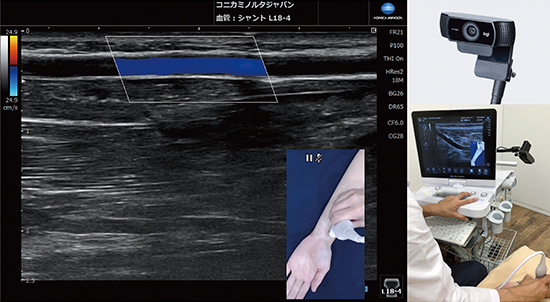

カメラリンクは,エコーに接続したカメラからの映像・画像をエコーに取り込む機能で,静止画や動画,カメラ内蔵マイクの音声を,エコー画像とともにリアルタイムで表示・保存できる機能である。スキャンの部位とエコー画像を同時に保存することで,臨場感を伴って検査の様子を再現することが可能となる(図2)。

図2 カメラリンク機能

透析領域などのバスキュラーアクセスにおいては,血管状態の把握と共有が欠かせない。一人の患者に対してチームで医療に当たっており,患者それぞれの血管の状態をシャントマップに記録し,情報の共有が行われている。カメラリンクを併用することで,エコー画像とその取得部位を明確に把握できるため,高いレベルでの情報共有が可能となる。失敗による再穿刺の防止や,コミュニケーション不足による患者からの信頼低下などを未然に防ぐことに役立つものと思われる。